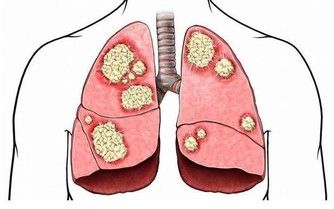

69歲的Bill Mcwhite,去年夏天到德克薩斯州莫斯科灣沿岸度假,本想著藉此機會好好放鬆一下自己,但整個旅程都被慢性阻塞性肺疾病(也稱為COPD)“破壞”!胸部出現阻塞症狀並伴隨著呼吸困難,這讓Bill不得不住進了醫院。

在德克薩斯州旅行結束後,Bill決定要仔細檢查一下自己的肺,畢竟他是一位有著55年菸齡的老煙民。在找到梅奧診所健康系統肺科的Adel Zurob醫生,醫生了解情況後建議Bill做一項肺癌篩查(低劑量CT)。檢查結果顯示:右肺有一個小的癌變結節。通過進一步的正電子發射斷層掃描(PEC-CT),顯示肺部以外沒有擴散或轉移的徵象。醫生建議,立即進行手術治療。

在醫生切除了Bill的癌變病灶後,還為他進行了胸部檢查以確定是否有淋巴結轉移的跡象,並對可疑的淋巴結進行了預防性切除。Zurob醫生說:“Bill的肺癌治癒的可能性極高,對Bill來講,沒有出現任何轉移是再好不過的了。”

梅奧診所近期公佈一項實驗調查,他們對梅奧診所的53000名)每年接受低劑量CT掃描或標準胸部X線檢查患者(均為重毒吸煙患者進行分析,結果顯示,接受CT掃描的患者比接受胸部X光檢查的患者肺癌死亡風險降低了20%。

Zurob醫生說:“如果肺癌早期篩查能夠用於每個菸齡30包年的患者,那麼每年我們可以避免2萬人的死亡,據“疾病預防控制中心”報導,美國每年有157,000人死於肺癌。這比任何其他類型的癌症都多”。